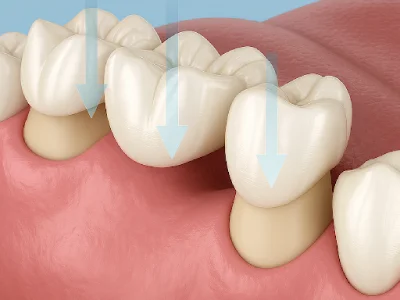

גשרים דנטליים מול שתלים

שיקום שיניים חסרות הוא לא רק עניין אסתטי, אלא גם בריאותי ותפקודי. גשרים ושיקום באמצעות שתלים דנטליים הם הפתרונות הנפוצים ביותר להשלמת שיניים חסרות, וכל אחד מהם מתאים למצבים שונים.